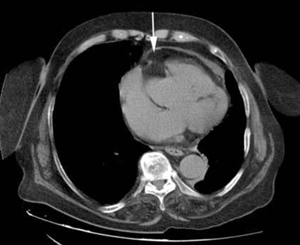

Se solicitó ecocardiografía transtorácica que mostró: fracción de eyección del ventrículo izquierdo (FEVI) 55%, ventrículo izquierdo con hipertrofia leve, hipoquinesia biventricular difusa, dilatación leve de aorta ascendente, aurícula izquierda moderadamente dilatada, engrosamiento pericárdico con probable derrame y colapso parcial de la aurícula derecha. Se solicitó tomografía de tórax (TC) sin contraste (figura 1) y (figura 2) que mostró una imagen típica de lipoma pericárdico, de 48 por 33 mm, que provocaba colapso de la aurícula derecha, considerándose la causa del taponamiento a baja presión. La angiografía coronaria no evidenció lesiones estenóticas significativas.